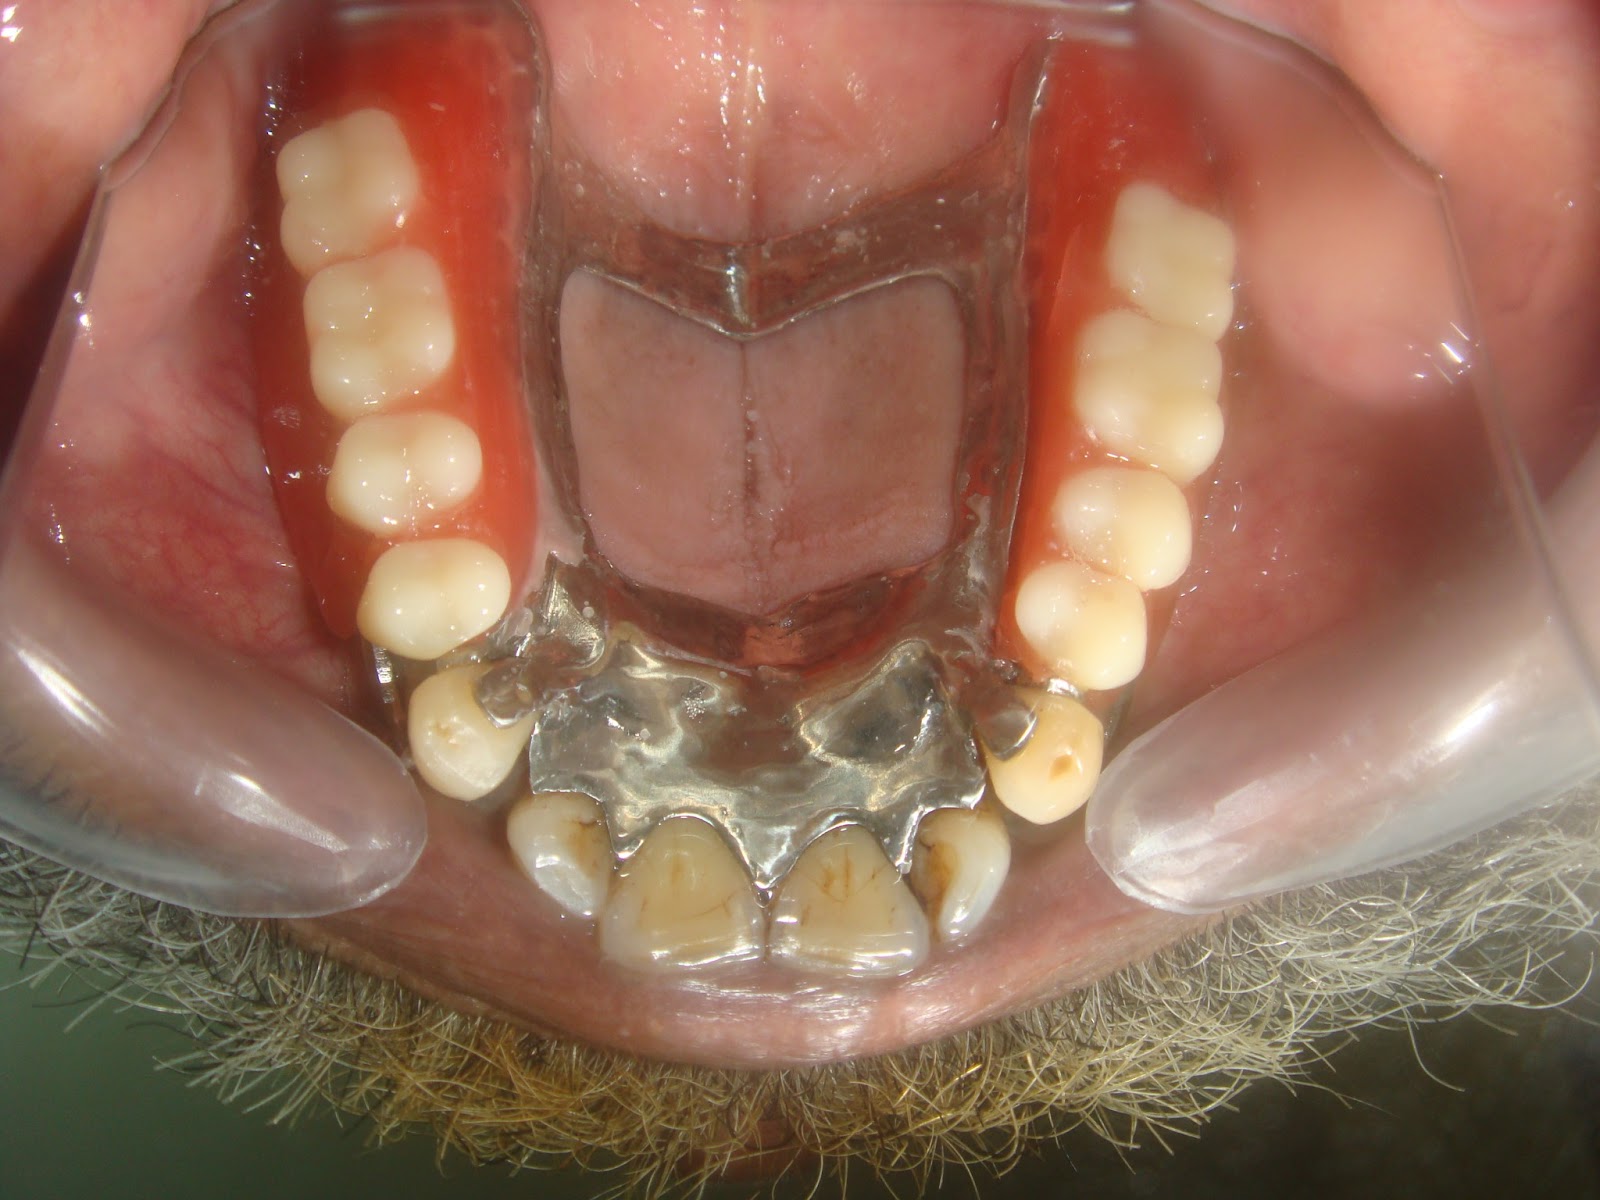

Lower Partial Denture Cast . a cast partial denture (cpd) is defined as a removable partial denture consisting of a cast metal framework that contains artificial teeth set in an. partial dentures, also known as removable partial dentures (rpd) or removable prostheses, are used to replace missing teeth in. cast metal partial dentures are the most common type of removable partial. the strategy of selecting component parts for a partial denture to help control movement of the prosthesis under. anyone who is missing some of their teeth, but not all of their teeth is eligible for a partial denture. That means that you can get partial. a cast metal partial denture replaces missing teeth and is fitted with the remaining teeth using metal clasps. while less sturdy than cast metal partial dentures, flexible partial dentures are valued for their comfort and flexibility.